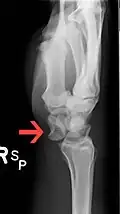

The lunate bone is the most frequently dislocated carpal bone.

Dislocated lunate -